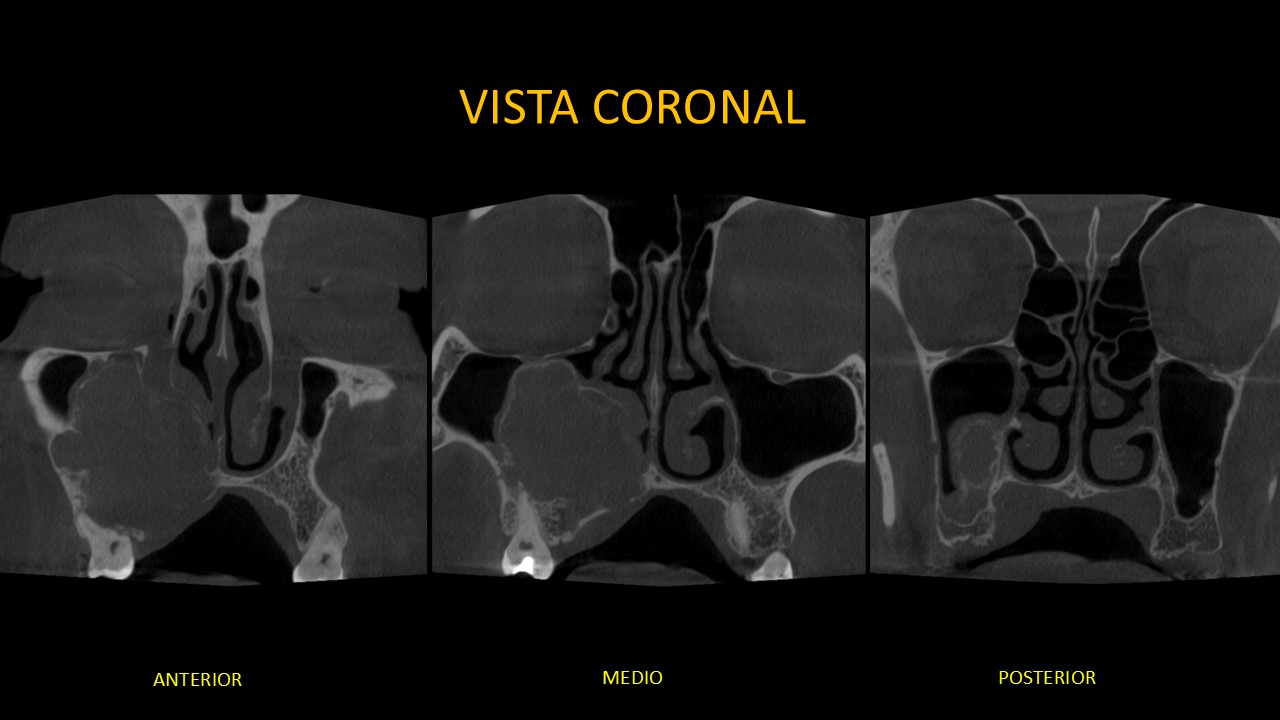

Figura 3

En la vista coronal (Figura 3) haciendo un barrido desde anterior a posterior evidenciamos que la lesión se extiende desde el piso de la órbita derecha, produciendo el borramiento parcial de la cortical inferior del conducto orbitario, hasta la tabla ósea palatina en zona de piezas 17-16, causando su adelgazamiento y borramiento parcial, sin embargo el ostium permanece permeable.

En una vista anterior podemos apreciar el desplazamiento del conducto nasolacrimal y de la pared externa de la fosa nasal, en la vista media, la fusión de la lesión con el cornete inferior y en la vista posterior el cornete inferior se encuentra conservado.